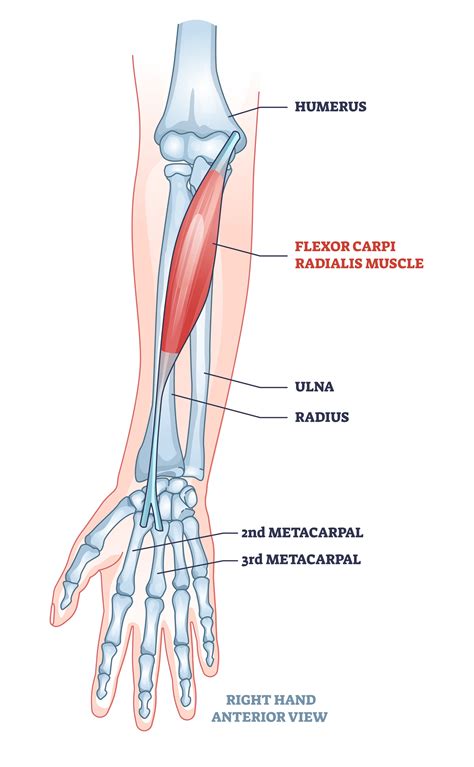

To grasp why injuries occur, it is helpful to visualize the anatomy. The Common Extensor Tendon serves as the origin point for several muscles in the forearm that are responsible for extending the wrist and fingers. It attaches these muscles to the lateral epicondyle, which is the bony bump on the outer side of your elbow.

The muscles that originate from this tendon include:

• Extensor carpi radialis brevis (ECRB)

• Extensor digitorum

• Extensor digiti minimi

• Extensor carpi ulnaris

Because multiple muscles converge and attach to this single point, the area is under constant tension during daily activities. Whether you are typing, lifting, or participating in racquet sports, this tendon is working continuously to stabilize and move your hand and wrist.